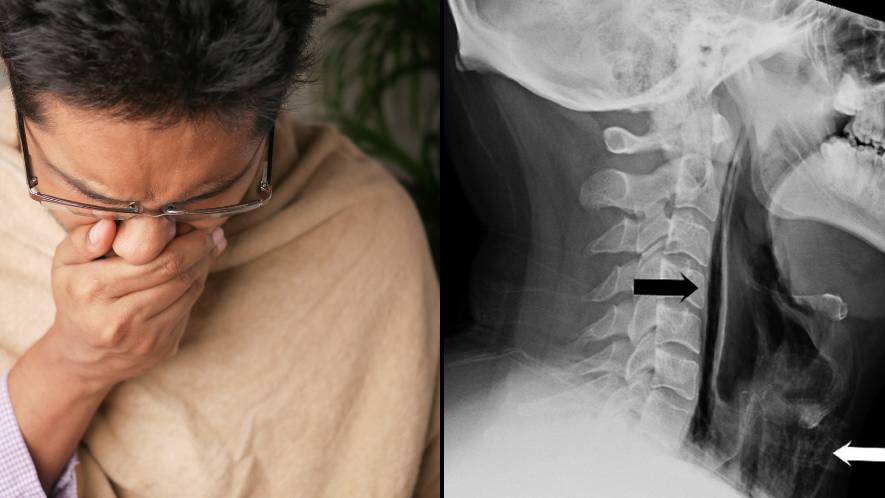

Man's Attempt to Hold in Sneeze Leads to Windpipe Tear

Originally Published 2 years ago — by Yahoo News

Doctors in the UK have reported the first documented case of a man tearing open his windpipe by holding in a sneeze. While serious cases of tracheal perforation can be life-threatening, the man made a full recovery after being treated with painkillers and allergy medication. Holding in sneezes can lead to various complications, including fractured ribs, ruptured eardrums, and burst blood vessels in the brain. Doctors advise against stifling sneezes and recommend sneezing into the elbow to prevent the spread of germs.

"Man Hospitalized After Holding in Sneeze Causes Throat Injury"

Originally Published 2 years ago — by LADbible

A British man was hospitalized after holding in a sneeze and blowing a hole in his throat. The man experienced a popping sensation and swelling in his neck after attempting to halt a forceful sneeze by pinching his nose and closing his mouth. Doctors discovered streaks of trapped air in his throat tissue, resulting in a self-inflicted throat rupture. Fortunately, the man recovered after receiving treatment with a feeding tube and antibiotics. The case serves as a reminder to catch, bin, and kill sneezes to avoid potential health risks.